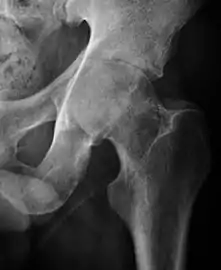

- Osteoarthritis

In adults, one of the main indications for radiographs is the detection of osteoarthritic changes (Figure 1(e)). Nevertheless, radiographs usually detect advanced osteoarthritis that can be graded according to the Tönnis classifications. The grading system ranges from 0 to 3, where 0 shows no sign of osteoarthritis. Intermediate grade 1 shows mild sclerosis of the head and acetabulum, slight joint space narrowing, and marginal osteophyte lipping. Grade 2 presents with small cysts in the femoral head or acetabulum, moderate joint space narrowing, and moderate loss of sphericity of the femoral head. Grade 3 is the severest form of osteoarthritis, which manifests as severe narrowing of the joint space, large subchondral cyst with productive bone changes that may lead to deformity of the bone components of the joint, while secondary osteoarthritis due to calcium pyrophosphate deposition can be diagnosed when calcification of hyaline cartilage and fibrocartilage is detected.[1]